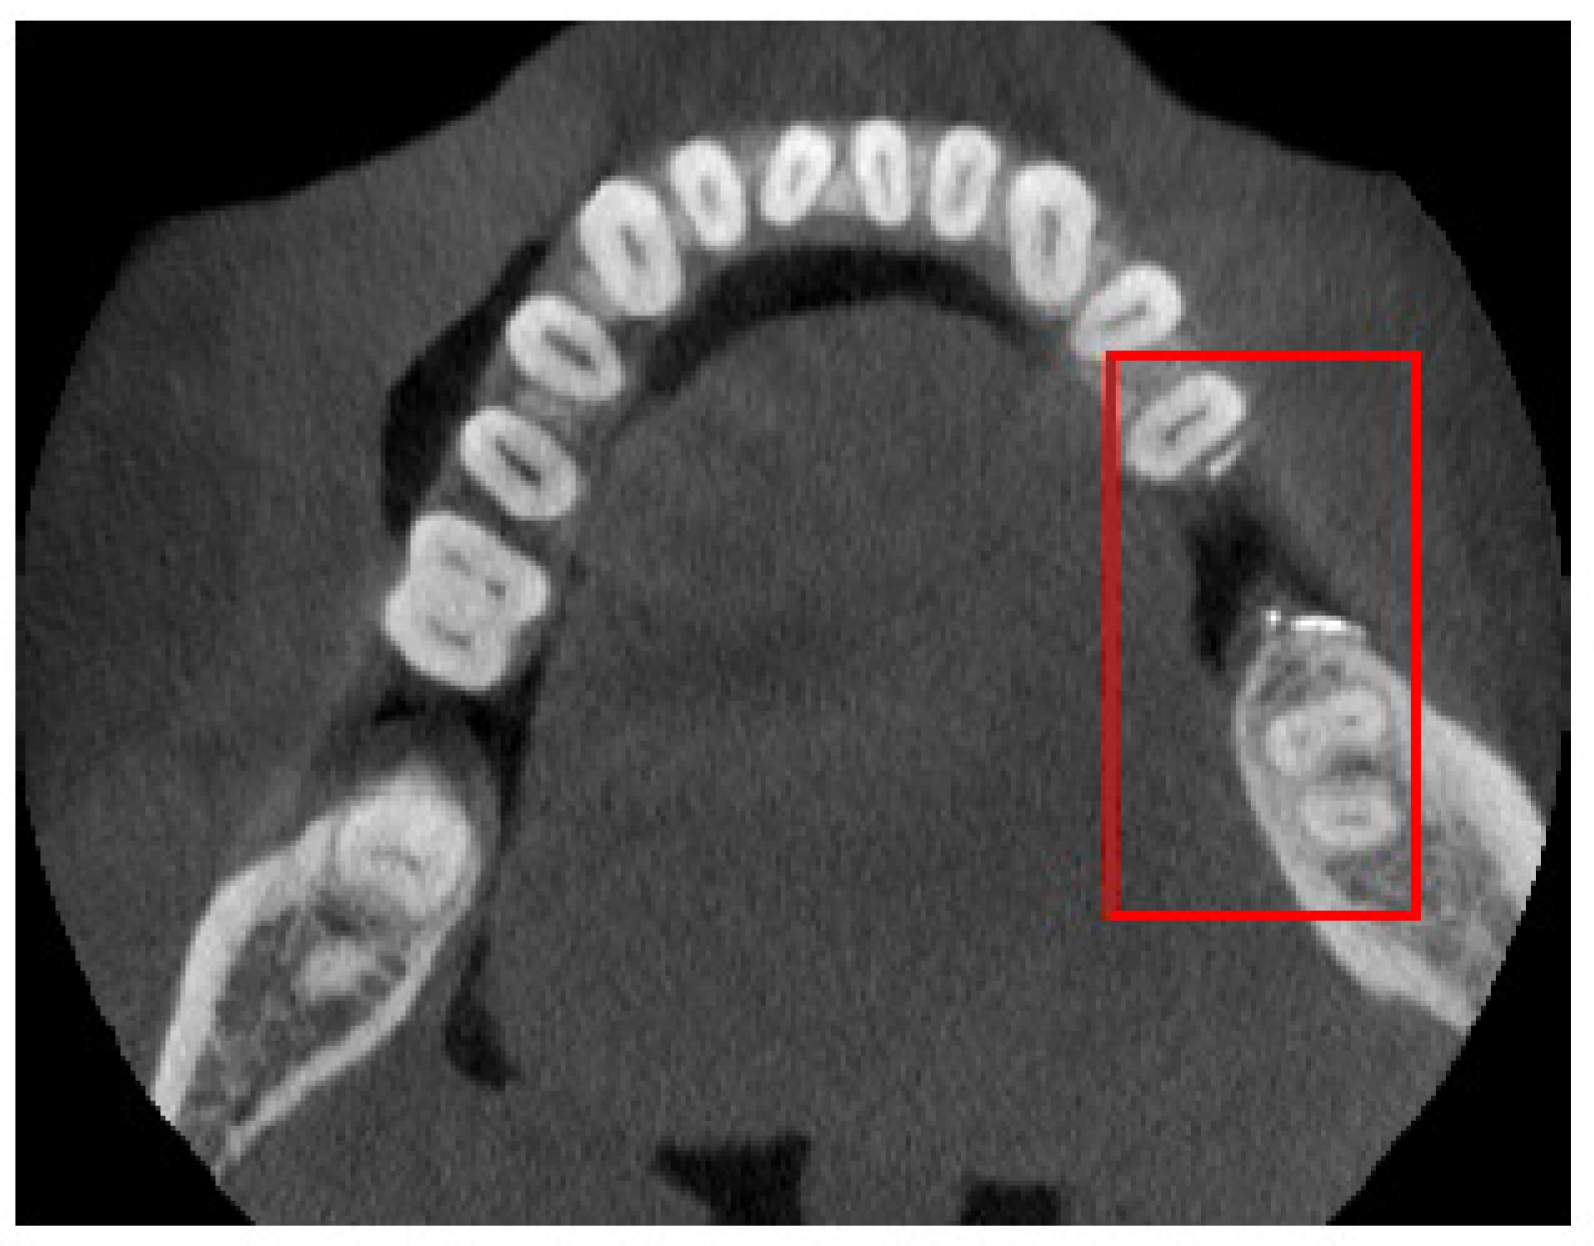

3. Numerical Results